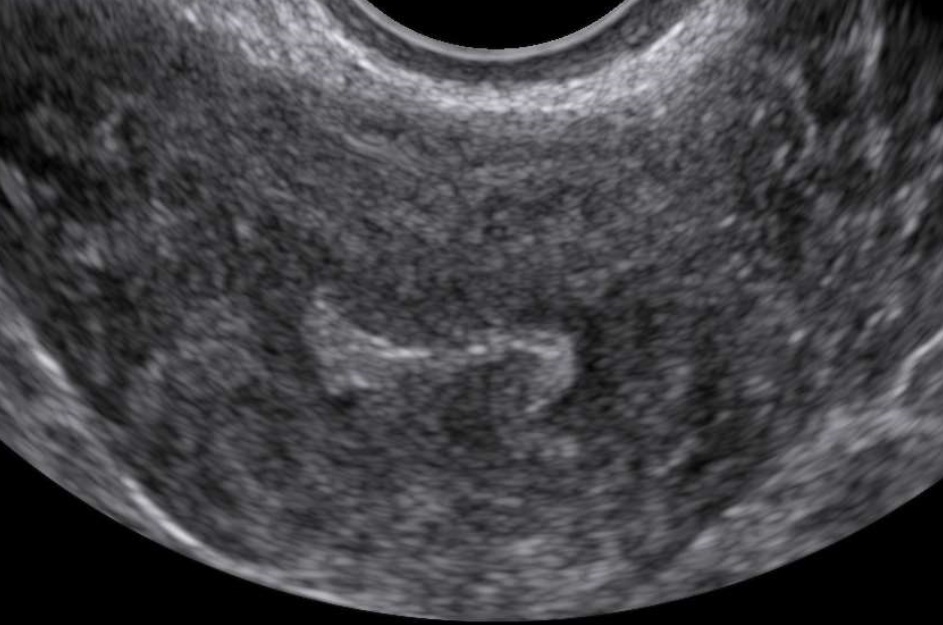

- Characteristics associated with adenomyosis according to the MUSA criteria (enlarged globular uterus, asymmetrical thickening of the myometrium, myometrial cysts, echogenic subendometrial lines and buds, hyperechogenic islands, fan shaped shadowing, an irregular or interrupted junctional zone, and translesional vascularity on color Doppler)

- Focal, diffuse, mixed-type, or adenomyoma (focal adenomyosis refers to cases where less than 25% of the myometrium of the corpus uteri is involved and more than 25% of the circumference of the lesion is surrounded by normal myometrium, estimated on that sagittal uterine section where the adenomyotic lesion appears the largest. When focal adenomyosis is distinctly demarcated and surrounded by hypertrophic myometrium, it is called an adenomyoma.)

- Cystic or non-cystic (cysts at least 2mm)

- Myometrial layer involvement (type 1: the junctional zone, type 2: the middle myometrium, type 3: the outer myometrium – the layer between the serosa and the vascular arcade)